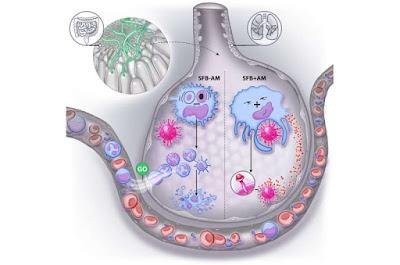

La composición de la microbiota intestinal influye en la susceptibilidad a las infecciones virales respiratorias y su gravedad. Las bacterias filamentosas segmentadas encontradas en los intestinos protegieron a los ratones contra la infección por virus de la influenza, virus sincitial respiratorio, y el SARS-CoV-2, causante del COVID-19.

Estas bacterias requerían la presencia de células inmunes en los pulmones, llamadas macrófagos alveolares residentes para mantener su protección contra la infección viral. La presencia de estas bacterias tuvo un impacto significativo en la resistencia a la infección por virus respiratorios en ratones con variaciones microbianas discretas.

En el estudio descubrieron complejas interacciones que vinculan la microbiota intestinal con la función de los macrófagos alveolares residentes, influenciando la gravedad de la infección por virus respiratorios. La presencia de una única especie bacteriana común en el intestino tuvo un gran impacto en modelos de infección viral respiratoria.